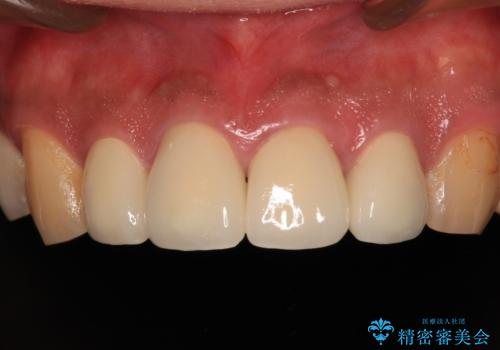

- 黄ばんだ前歯や目立つ奥歯の銀歯をきれいにしたいとのことで来院された患者様です。

小さい修復物の銀歯が装着されている歯はセラミックインレーにて、その他はオールセラミッククラウンにて補綴治療を進めることとしました。